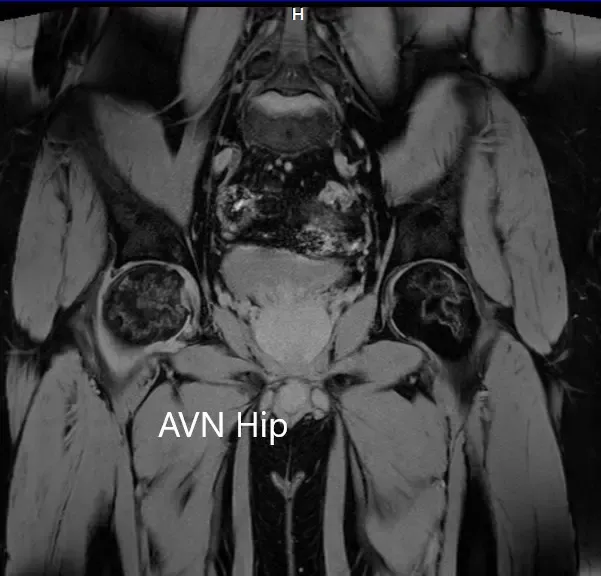

Sección coronal T1WI de la resonancia magnética que muestra AVN en cadera.

Sección coronal T2WI de la resonancia magnética que muestra AVN de cadera.

Secciones axiales de la T2WI y T1WI de la MRI.

Había zonas hipointensas tanto en T1WI como T2WI en ambas cabezas del fémur, sugestivas de esclerosis. Había edema de médula ósea circundante y la zona necrótica bilateral era aproximadamente del 70%.